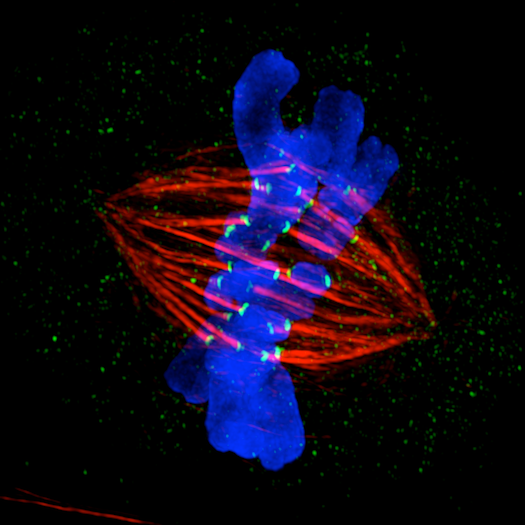

HIV, cancer, malaria, and more, up close--plus some non-killers, to show what this new microscopy system can do.

At three Australian universities, a new tool is allowing researchers to see things that have never been seen before. GE’s superfancy new microscope, the DeltaVision OMX Blaze, is designed to see deep into cells to learn exactly how diseases work. Says GE:

The OMX, which GE launched in late 2011, uses a combination of optics and powerful computer algorithms to crash though the diffraction barrier, long thought as the limit for the resolution of optical microscopes. (The barrier stops microscopes from distinguishing between two objects separated by less than approximately half the wavelength of light used to image them.) The GE technique, called 3D structured illumination microscopy (SIM), more than doubles the resolution in all three dimensions. The result is that the OMX can see objects as small as 100 nanometers, ten times smaller than the typical germ.

They’ve been specifically looking at malignant items in the body: cancerous cells, viruses like HIV, and dangerous bacteria. Click through to our gallery to see these killers in more detail than you’ve ever seen before.

Cancer